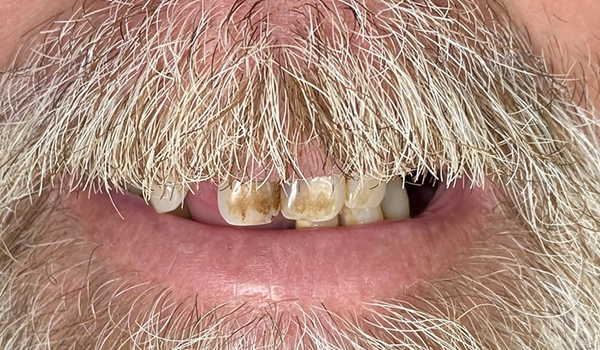

Before

After